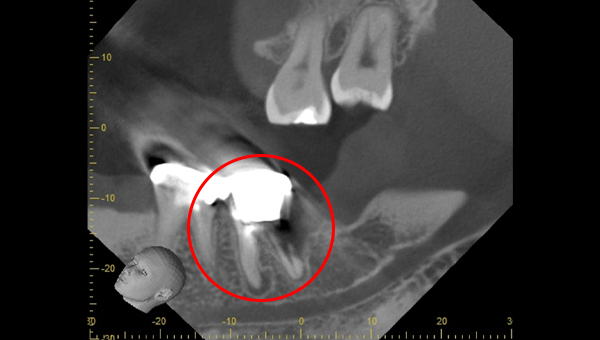

CT像①

CT像②

説明:

CT像です。根の中央を超えて虫歯が広がっているのがわかります。そこに上の親知らずを移植することに

しました。